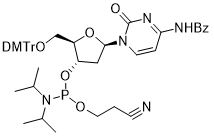

馬鞍山致研生物醫(yī)藥科技有限公司成立于馬鞍山市鄭浦港新區(qū)現(xiàn)代產(chǎn)業(yè)園。公司專(zhuān)注于生物小分子、醫(yī)藥中間體相關(guān)產(chǎn)品的研發(fā)和生產(chǎn),產(chǎn)品主要包括DNA亞磷酰胺單體、RNA亞磷酰胺單體、特殊單體以及按照客戶(hù)要求定制的RNA和DNA,并且公司提供定制合成等方面的研究服...

馬鞍山致研生物醫(yī)藥科技有限公司成立于馬鞍山市鄭浦港新區(qū)現(xiàn)代產(chǎn)業(yè)園。公司專(zhuān)注于生物小分子、醫(yī)藥中間體相關(guān)產(chǎn)品的研發(fā)和生產(chǎn),產(chǎn)品主要包括DNA亞磷酰胺單體、RNA亞磷酰胺單體、特殊單體以及按照客戶(hù)要求定制的RNA和DNA,并且公司提供定制合成等方面的研究服...